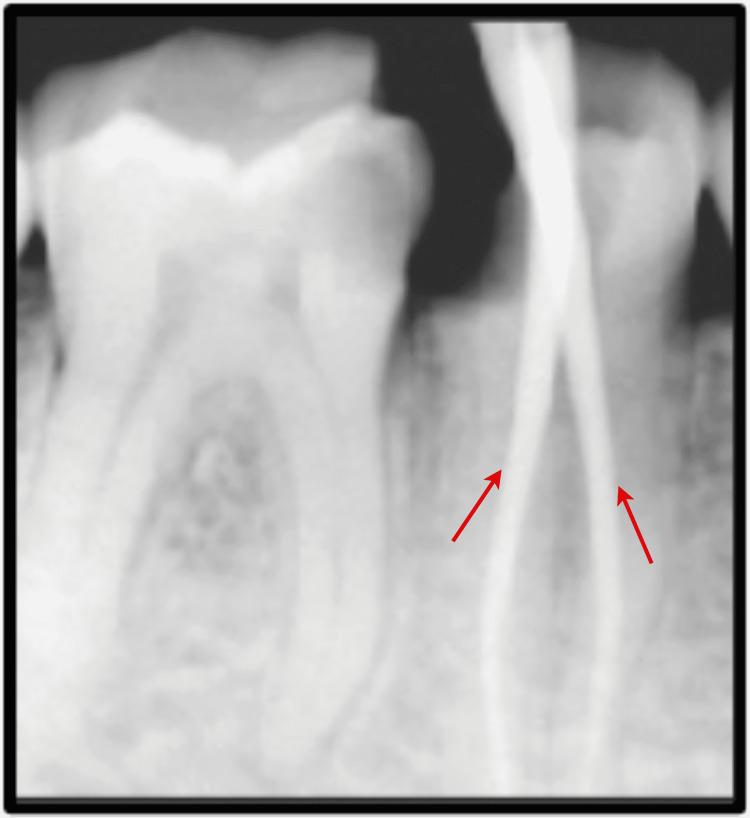

Two Rooted Mandibular Second Premolar: An Unusual Finding.

Understanding the root and canal anatomy is pivotal before initiating endodontic surgical procedures. Any missed canal will cause treatment failure and ultimately lead to tooth extraction in this era of tooth conservation. Mandibular second premolars have attracted researchers and clinicians for having aberrant anatomy. Variations in the number of roots or canals may not be discerned on 2D radiographs and may become apparent during treatment procedures. The occurrence of two roots in the lower second premolar has been reported in the current case. Here, in this case, the authors have described the clinical course of the patient along with the management of these two rooted mandibular second premolars.